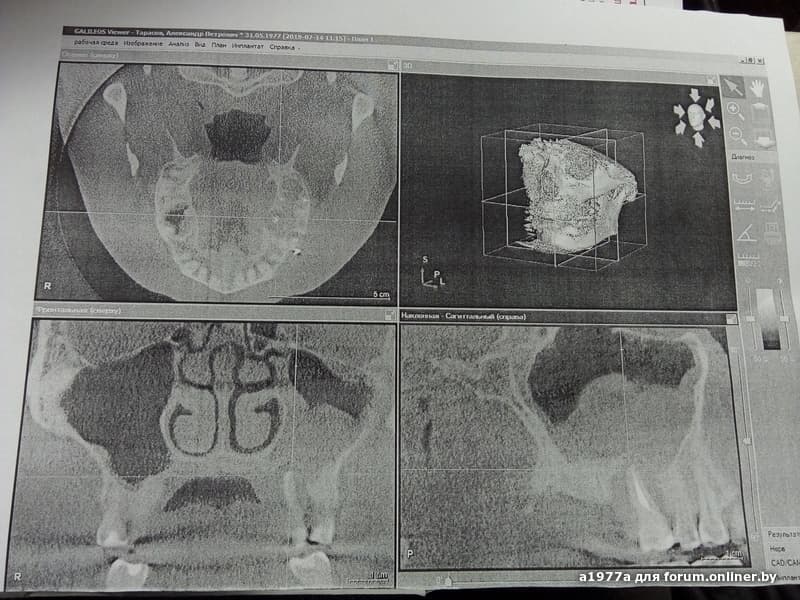

Здравствуйте,ситуация такая:есть киста у корней 26-го зуба,проросшая в гайморовую пазуху ,ну и односторонний одонтогенный синусит.Зуб под удаление,пазуху чистят,всё зашивают.Врач спрашивает имплант буду ставить или съемный протез,т.к.от этого зависит как будут делать операцию и при классической операции потом невозможно будет поставить имплант.Ворос:чем отличаются операции и всё-таки имплант же лучше?Или делать классическую операцию в моем случае?Просто в этом вопросе вообще не разбираюсь.Спасибо.

скиньте снимок

Вот только такой есть,а остальная клкт на диске

лучше делать все по максимуму, как будто ставить имплант будете, а съемник всегда получится